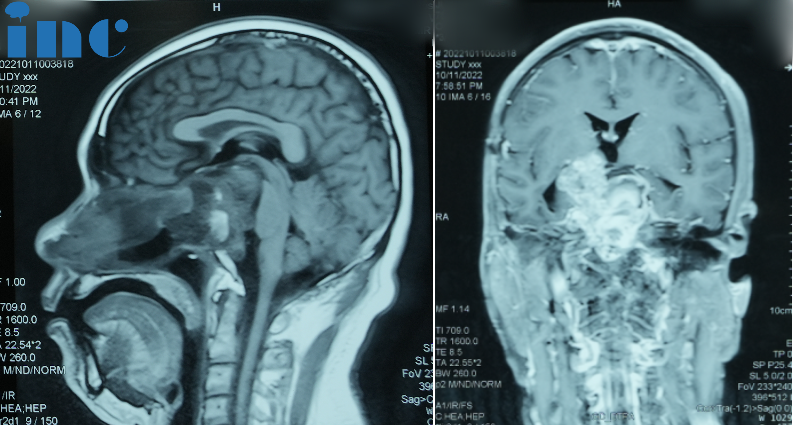

2022年7月,患者三次出现同样症状,磁共振检查再次提示鞍区肿瘤复发。因患者不想再接受开颅手术,10月8日全麻下行经鼻内镜肿瘤切除术。术后病理为脊索瘤复发。术后因患者忘记服用醋酸泼尼松,导致内分泌功能紊乱,出现嗜睡、精神萎靡的症状,伴有脑脊液增多颅内压增高。遂于同年11月19日行脑脊液分流术,后症状缓解消失。

2023年1月底,患者四次出现之前的症状,4月份开始自感上下肢力量下降,患者可自行站立和行走,但自感不稳。

术前:肿瘤体大,广泛累及颅底结构,侵蚀斜坡、鞍内鞍上、海绵窦区,包裹右侧颈内动脉。肿瘤向上推挤视神经、视交叉,到达三脑室底部;向后上方推挤脑干和基底动脉,部分肿瘤边缘与脑干分界欠清。